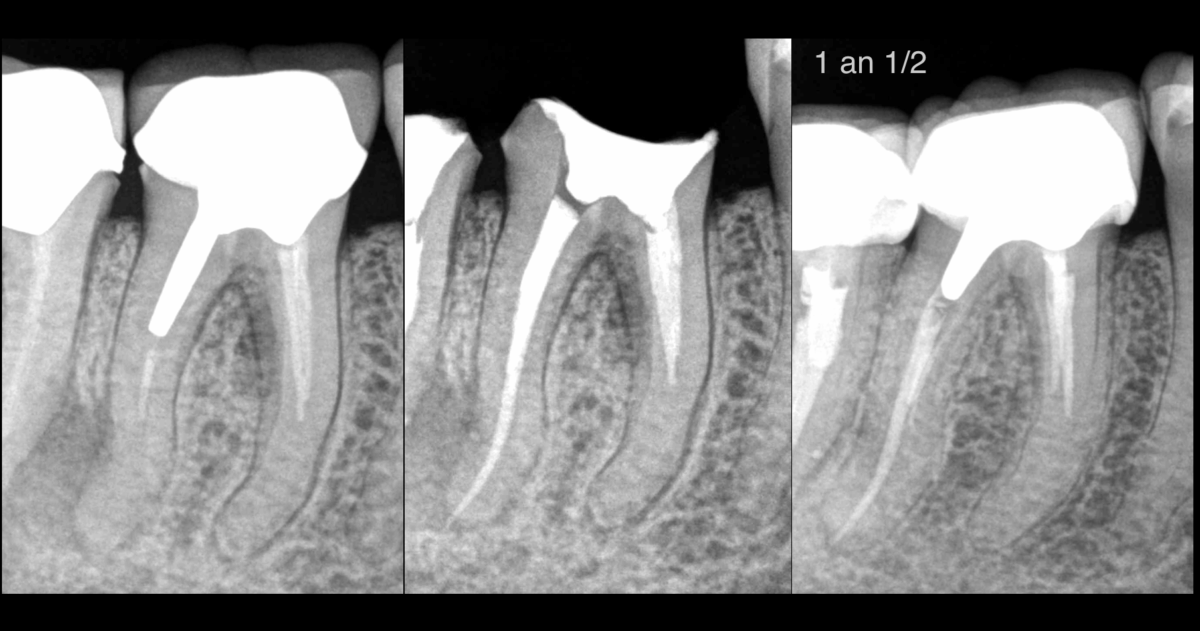

📸 À 1 an ½ :

✅ 𝐆𝐮𝐞𝐫𝐢𝐬𝐨𝐧 𝐝𝐞 𝐥𝐚 𝐥𝐞́𝐬𝐢𝐨𝐧 𝐚𝐩𝐢𝐜𝐚𝐥𝐞 𝐞𝐭 𝐥𝐚𝐭𝐞́𝐫𝐨-𝐫𝐚𝐝𝐢𝐜𝐮𝐥𝐚𝐢𝐫𝐞

✅ 𝐆𝐮𝐞𝐫𝐢𝐬𝐨𝐧 𝐝𝐞 𝐥𝐚 𝐥𝐞́𝐬𝐢𝐨𝐧 𝐝𝐞 𝐥𝐚 𝐟𝐮𝐫𝐜𝐚𝐭𝐢𝐨𝐧 𝟒𝟔